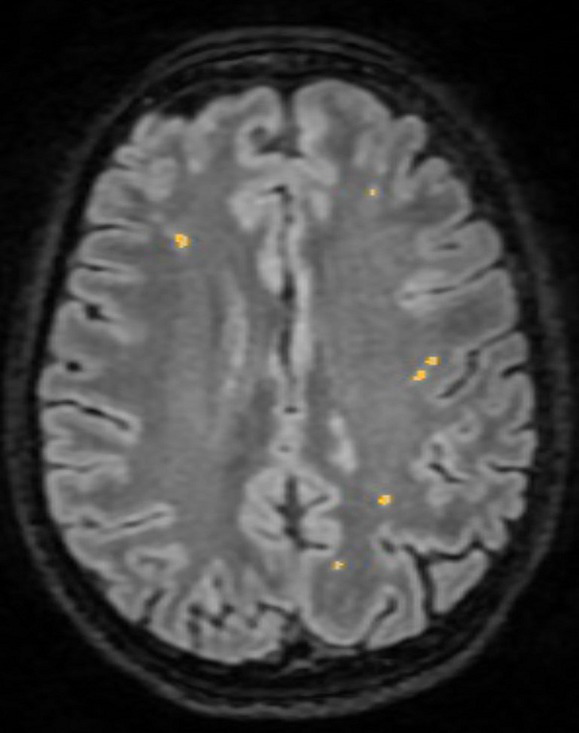

In order to be compatible with the image processing software and thus accepted in the study, MRI studies had to be performed on either 1.5 or 3 Tesla MRI machines, with a non-contrast enhanced 3D T2-FLAIR acquisition with an inversion time of 2,250 ms, an echo time of 140 ms, a voxel size ranging between 1 and 3, and a slice thickness of 1.5–3 mm; patients with examinations utilizing filters such as GE filter SCIC and GE filter E were excluded from the study due to incompatibility with the software. MRI images were assessed using the semi-automated software Quantib ND™ to measure WM lesional volume. Quantib ND™ was selected for its advanced artificial intelligence (AI) algorithms, which facilitate accurate and efficient quantification of brain lesions. The process involved uploading the MRI scans into the software, where Quantib ND’s AI algorithms semi-automatically identified and measured the WM lesions. Any necessary manual adjustments were made to ensure accuracy, following which the software provided quantitative data on lesional volume. This data were then extracted for statistical analysis. For each of the 3D FLAIR acquisitions, each of the T2 weighted hyperintensity, surrounded by normal isointense WM, was marked (Figure 2). Lesions located in the basal ganglia and brainstem were excluded from measurement, as they were ascribed to small vessel disease. Measurement protocol for patients with stroke comprised two phases: initially, all cerebral lesions were automatically identified and measured, including the volume of the stroke; subsequently, the volume of the stroke was excluded, and the remaining volumes were recorded. Two examiners, a trained neurologist (RȘB) and a radiologist (ANM), conducted all examinations.

Figure 2

White matter lesion identification using Quantib ND™.